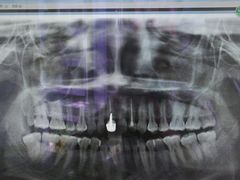

• 德伦口腔

• -德伦口腔

Gattaca | 17-04-30

报错